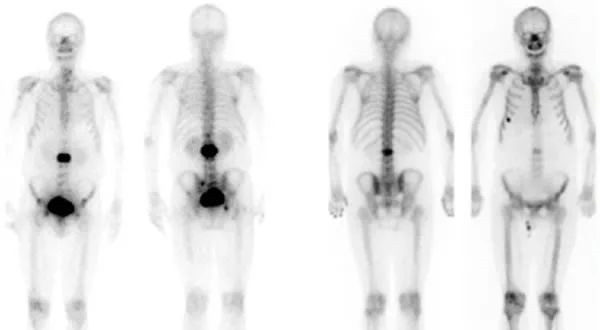

PET/CT的掃“癌”行動

影像檢查是輔助臨床診斷、重大疾病早期檢查的重要手段,特別是對腫瘤、心腦血管疾病的早發(fā)現(xiàn)、早診斷具有重大意義。 閱讀量:2568